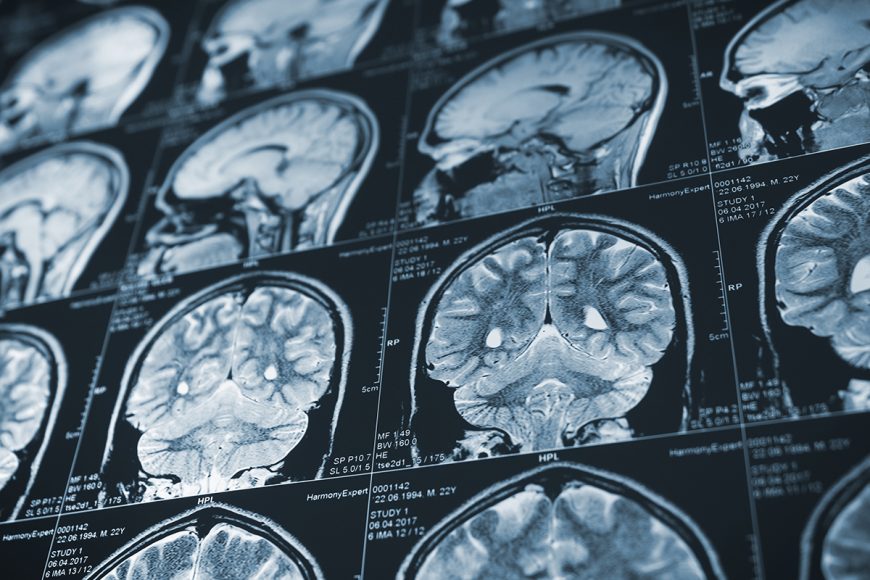

Gathering data from CT scans can be labour intensive and exhaust health care resources. Queen’s researchers Amber Simpson and Farhana Zulkernine along with radiologist Richard Do (Memorial Sloan Kettering Cancer Center, New York) are developing technology that will relieve these issues, as well as predict how cancer will spread in patients, using natural language processing.

Natural language processing (NLP) is used to program computers to process and analyze large amounts of language data from interactions between humans and computers. Dr. Simpson (School of Computing; Biomedical and Molecular Sciences) and Dr. Zulkernine (School of Computing) have leveraged the data scraping abilities of NLP, applying the technology to CT scans to predict where cancer could spread.